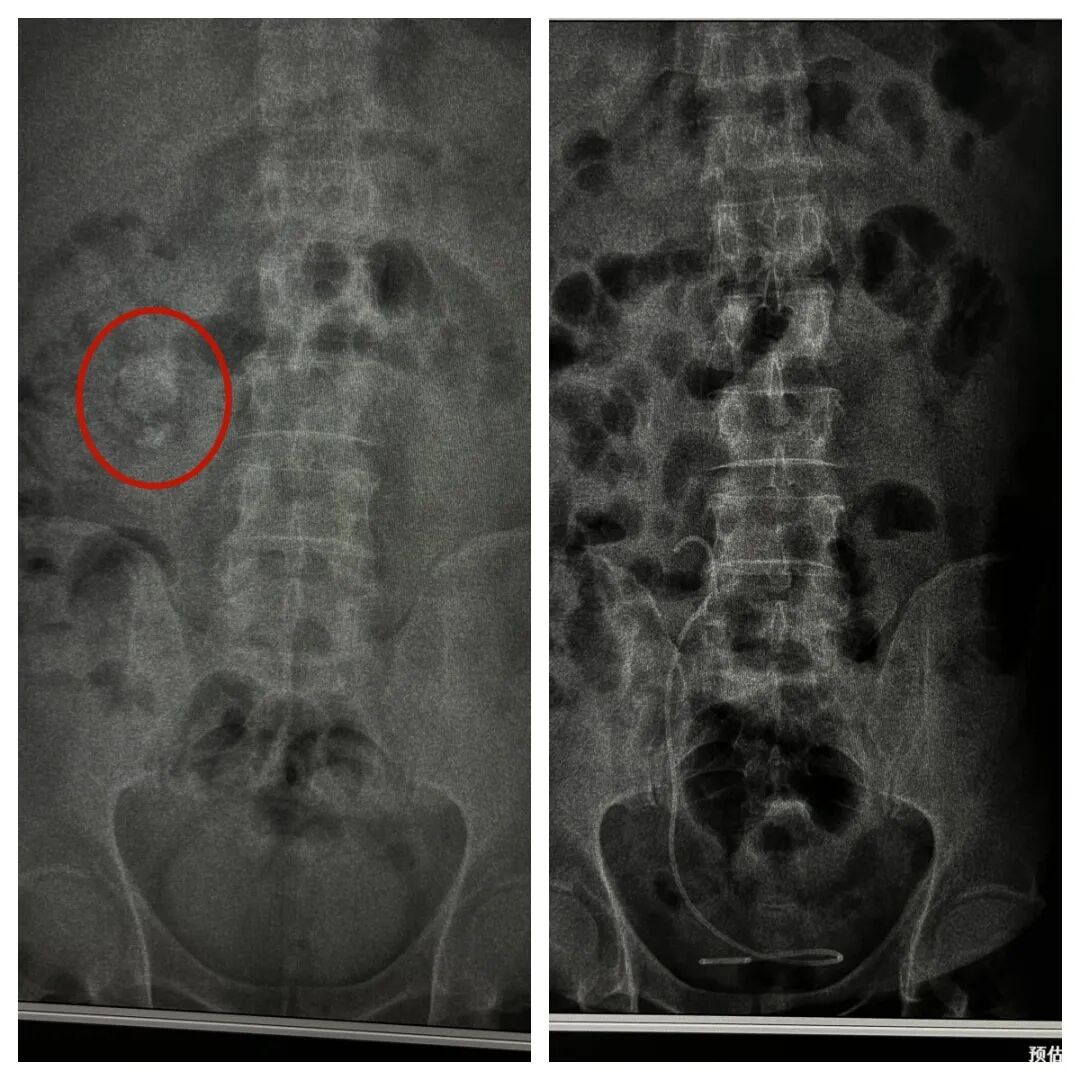

据悉,患者为40岁男性,20天前无明显诱因出现右侧腰腹部间断性疼痛,还伴有尿急、尿频、尿痛等不适症状,起初未予重视,随着症状逐渐加重,严重影响正常生活,遂前往我院就诊。接诊医生详细询问病史并完善相关检查后,初步诊断为右侧肾结石伴有积水和感染,同时发现患者还患有高血压2级、2型糖尿病,且体型偏胖,这些情况无疑增加了诊疗难度。

“患者的病情较为复杂,结石合并肾盂感染,本身就存在感染扩散的风险,再加上糖尿病会导致机体免疫力下降、伤口愈合缓慢,高血压则会增加术中出血、术后心脑血管并发症的概率,而且患者体型偏胖,经皮肾镜手术需要翻身操作,对手术体位的摆放和术中视野的暴露都提出了更高要求。”泌尿外科主任介绍道,术前检查尿常规提示感染较重,进一步提示感染情况较为严重,若不及时干预,可能引发严重并发症,危及生命。

经过充分的术前准备,手术如期开展。术中,在麻醉科团队的密切配合下,泌尿外科医生凭借精湛的技术,精准定位穿刺点,成功建立经皮肾通道。术中探查发现,患者肾脏内脓苔较多,结石表层的灰黄色附着物影响操作视野,医生小心翼翼地清理脓苔,再利用激光设备将结石击碎,随后逐步将碎石取出,最后顺利置入输尿管支架管,保障尿路通畅。整个手术过程顺利,耗时较短,术中出血量少,未出现任何严重并发症。